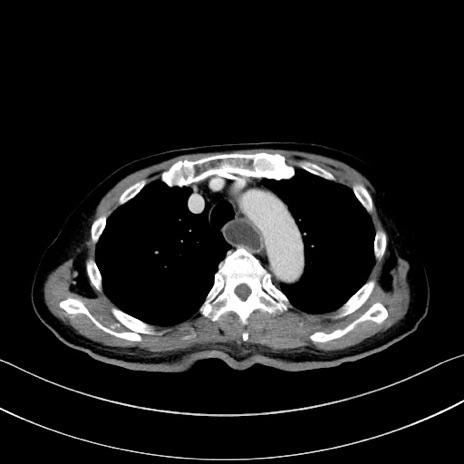

症例28(横断像)

【症例】60歳代男性

【主訴】嘔吐

【現病歴】胃癌にて胃全摘後。食思不振が悪化し、夜中に嘔吐することがある。

【既往歴】胃癌、胃全摘、脾摘、胆摘後

【データ】WBC 5900、CRP 10.56